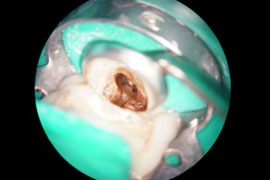

Der zu behandelnde Zahn wird vor dem Eingriff örtlich betäubt, so dass Sie von dem Eingriff nichts spüren. Während der Behandlung wird der Zahn durch ein Gummituch (Kofferdam) isoliert. Dies ermöglicht ein sauberes, übersichtliches Arbeiten und schützt Sie vor Instrumenten (Aspiration) und schlecht schmeckenden Spüllösungen. Die Wurzelkanalbehandlung wird mit Hilfe eines Dentalmikroskops durchgeführt. Durch die Vergrößerung ist es möglich feinste Strukturen des Wurzelkanalsystems einzusehen, aufzubereiten, zu desinfizieren und bakteriendicht zu verschließen.

Entscheidend für den Erfolg der Wurzelkanalbehandlung ist die komplette Aufbereitung und Desinfektion des gesamten Wurzelkanalsystems. Die Aufbereitung der Kanäle bis an die Wurzelspitze erfolgt mit Stahl-Feilen, Ultraschall und hochflexiblen Nickel-Titan-Feilen. Dabei finden neben Handfeilen auch maschinelle Aufbereitungssysteme (drehmomentgesteuerte Feilen) ihre Anwendung. Die Bestimmung der Arbeitslänge erfolgt elektrometrisch und wird während der gesamten Therapie gemessen und kontrolliert.

Sehr lange, enge oder verzweigte Wurzelkanäle sind keine Seltenheit und die Desinfektion ist mit einem höheren Aufwand verbunden. Ein Dentalmikroskop, die elektrometrische Längenmessung, sowie ein Ultraschallgerät mit unterschiedlichen Arbeitsinstrumenten sind für den Erfolg der Behandlung wichtige Hilfsmittel.

4. Kanal an einem Oberkiefer-Molaren